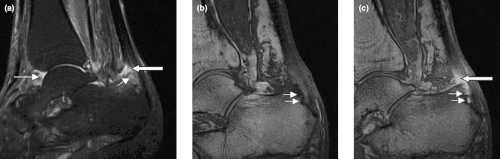

Enthesitis is inflammation of the entheses (singular: enthesis), the sites where tendons, ligaments and joint capsules attach to bones.[1][2]

It is a type of enthesopathy, meaning any pathologic condition of the entheses, with or without inflammation. There are some cases of isolated, primary enthesitis which are very poorly studied and understood. It is known to be associated with other autoimmune diseases, like spondyloarthropathies and psoriasis (thought to often precede psoriatic arthritis). A common autoimmune enthesitis is at the heel, where the Achilles tendon attaches to the calcaneus.